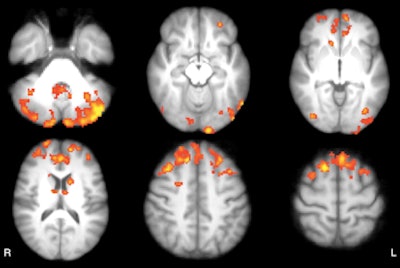

As one might expect, baseline resting-state fMRI showed that MS patients had significantly lower functional connectivity clusters in the cerebellum, frontal and occipital cortices, caudate nucleus, and thalamus than the healthy subjects.

However, there was no significant difference in baseline functional connectivity maps of the thalamic resting-state network between the waitlist and intervention groups. The scans covered the cerebellum, thalamus, basal ganglia, and cingulate, frontal, temporal, occipital, and bilateral parietal cortices.

After the eight-week rehabilitation program, patients in the intervention group exhibited functional connectivity changes that correlated with improvements in sustained attention and executive function. By comparison, patients in the waitlist group, who did not participate in the video game training, showed no such changes.

"The improvement in cognitive performance positively correlated with the functional connectivity increase in cortical areas belonging to the posterior components of the default mode network and negatively correlated with the functional connectivity decrease in cerebellar areas," the authors wrote.